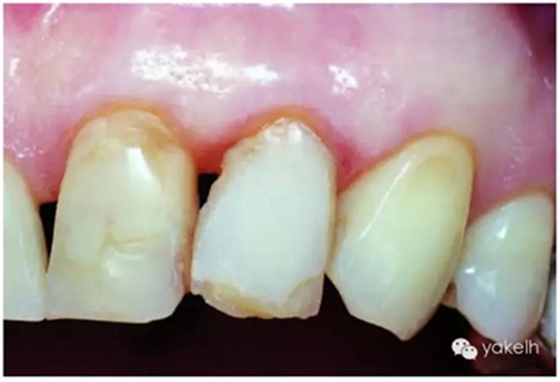

圖2.36大顆粒填料復合樹脂制作的不良修復體。

圖2.37紫外線光下,牙體組織熒光升高而修復體熒光效應全部缺失

修復體看起來很暗,沒有熒光效應。